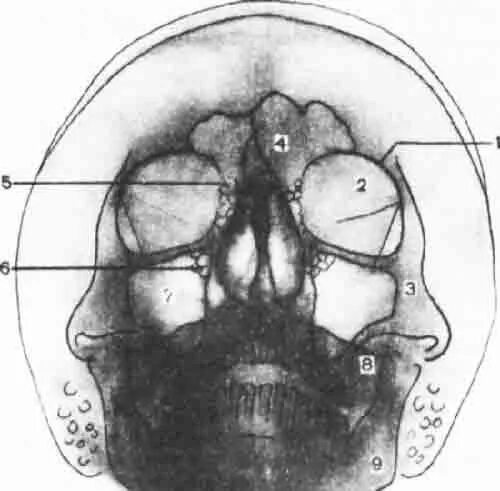

Снимок черепа в прямой проекции